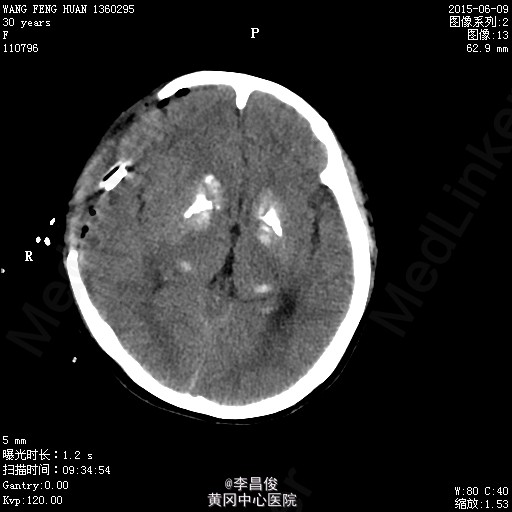

入院完善相关检查:血常规:血红蛋白 105.1g/L,血小板 95*10^9/L,尿常规:蛋白 -,肝功能:谷丙转氨酶 77.9U/L,尿酸 426.7umol/L,凝血机制:D-二聚体 2267ng/ml。 血脂:甘油三酯:3.31;低密度脂蛋白:5.46,甲功、心肌三项、心脏彩超正常, 给予对症处理,患者于6月4 日8:42分在会阴左侧切下以LOA位顺利娩出一活女婴,产程顺利,产时血压最高达160/110mmHg,给予心痛定一粒舌下含服,产后回病房后监测血压在100-140/70-90mmHg之间波动。6月7日5点多头痛明显,急查头部CT提示:右侧额颞顶部硬模下血肿。请神经外科急会诊,建议转专科治疗。转外科后,患者意识障碍加重,6月8日17:30时急诊全麻下行“右侧开颅硬膜下血肿清除+去骨瓣减压术”,术后转重症医学科。稳定后拔除气管插管后转回专科,行抗感染、止血、神经营养、脱水治疗,定期换药及CT复查,后出现癫痫发作,给予抗癫痫治疗。6月13日患者癫痫发作后呈持续状态,药物控制不理想,故转入ICU进一步监护治疗。患者神志昏迷,给予持续泵入丙戊酸钠、咪达唑仑控制抽搐,适当脱水、抗感染、营养支持及对症处理,并及时复查相关检查。患者癫痫控制后于17/6日顺利拔除气管导管。于17/6日再次癫痫发作1次,很快缓解。转神经科继续治疗:患者神志清楚,精神、食欲一般,诉左侧肢体无力伴麻木,无抽搐发作,右侧肢体肌力尚可,左侧肢体肌力3级。肌张力不高。继续给予抗癫痫、适当抗感染、肢体康复训练及对症支持治疗,一周后行颅脑MRI:未见明显异常;查体:心肺听诊(-),腹软,压痛反跳痛,双下肢无水肿,右侧肢体肌力尚可,左侧肢体肌力5级-,病理征(-),给予办理出院。

患者产前产后血压基本维持在正常水平,尿蛋白阴性,癫痫可能与额颞部出血相关性大,双侧基底节区对称行钙化有可能是Fahr综合征,为遗传性疾病,家族是否有类似病例?

外出逛街出现自觉头晕头痛,予解痉等治疗后,症状有没有缓解?术中血压没有控制好,可能诱发了硬膜下血肿,进而出现癫痫。